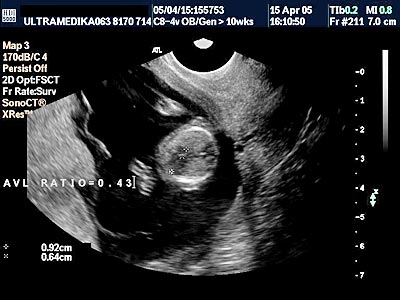

B) Drugi marker je registrovanje postojanje povećane debljine prozračne zone (NT) u vratu ploda-embriona. Obično greške nastaju kada se kontura vrata ploda ne razlikuje od amniona - opne u kojoj se plod nalazi. Osim znanja doktora, rezolucija slike Ultrazvučnog aparata čini ključnu ulogu u merenju ove strukture. Ona-NT se meri u periodu od 9 do 14 GN. Iako je najveća normalna debljina NT 2,5 mm na kraju 14 GN ova vrednost NT može ukazivati na trizomiju ako je registrovana na početku ovog vremenskog perioda. Samo Ultrazvučna kompjuterizovana tomografija može u velikom procentu pouzdano izmeriti ovu strukturu i to na dva načina. Pregled endovaginalnom sondom Braund-band od 8-4MHz, često zbog pozicije ploda nije u stanje da adekvatno registruje NT. Pregled se može znatno zbog toga produžiti i ne mora tačno izmeriti debljinu NT. Međutim u ovakvim situacijama upotrebom Braund-band sondi koje koriste ceo opseg ultrazvučnih talasa od 12 do 5 MHz, pregled se u velikom broju slučajeva završava pregledom preko prednjeg trbušnog zida. Ovaj transabdominalni pregled ima prednosti zbog mogućnosti boljeg pozicioniranja ultrazvučne sonde

u odnosu na položaj ploda, pri čemu je kvalitet slike neuporedivo bolji u odnosu na pregled vaginalnom sondom. Jedino konstitucija trudnice donekle ograničava pregled preko prednjeg trbušnog zida (mokraćna bešika ne mora biti puna).